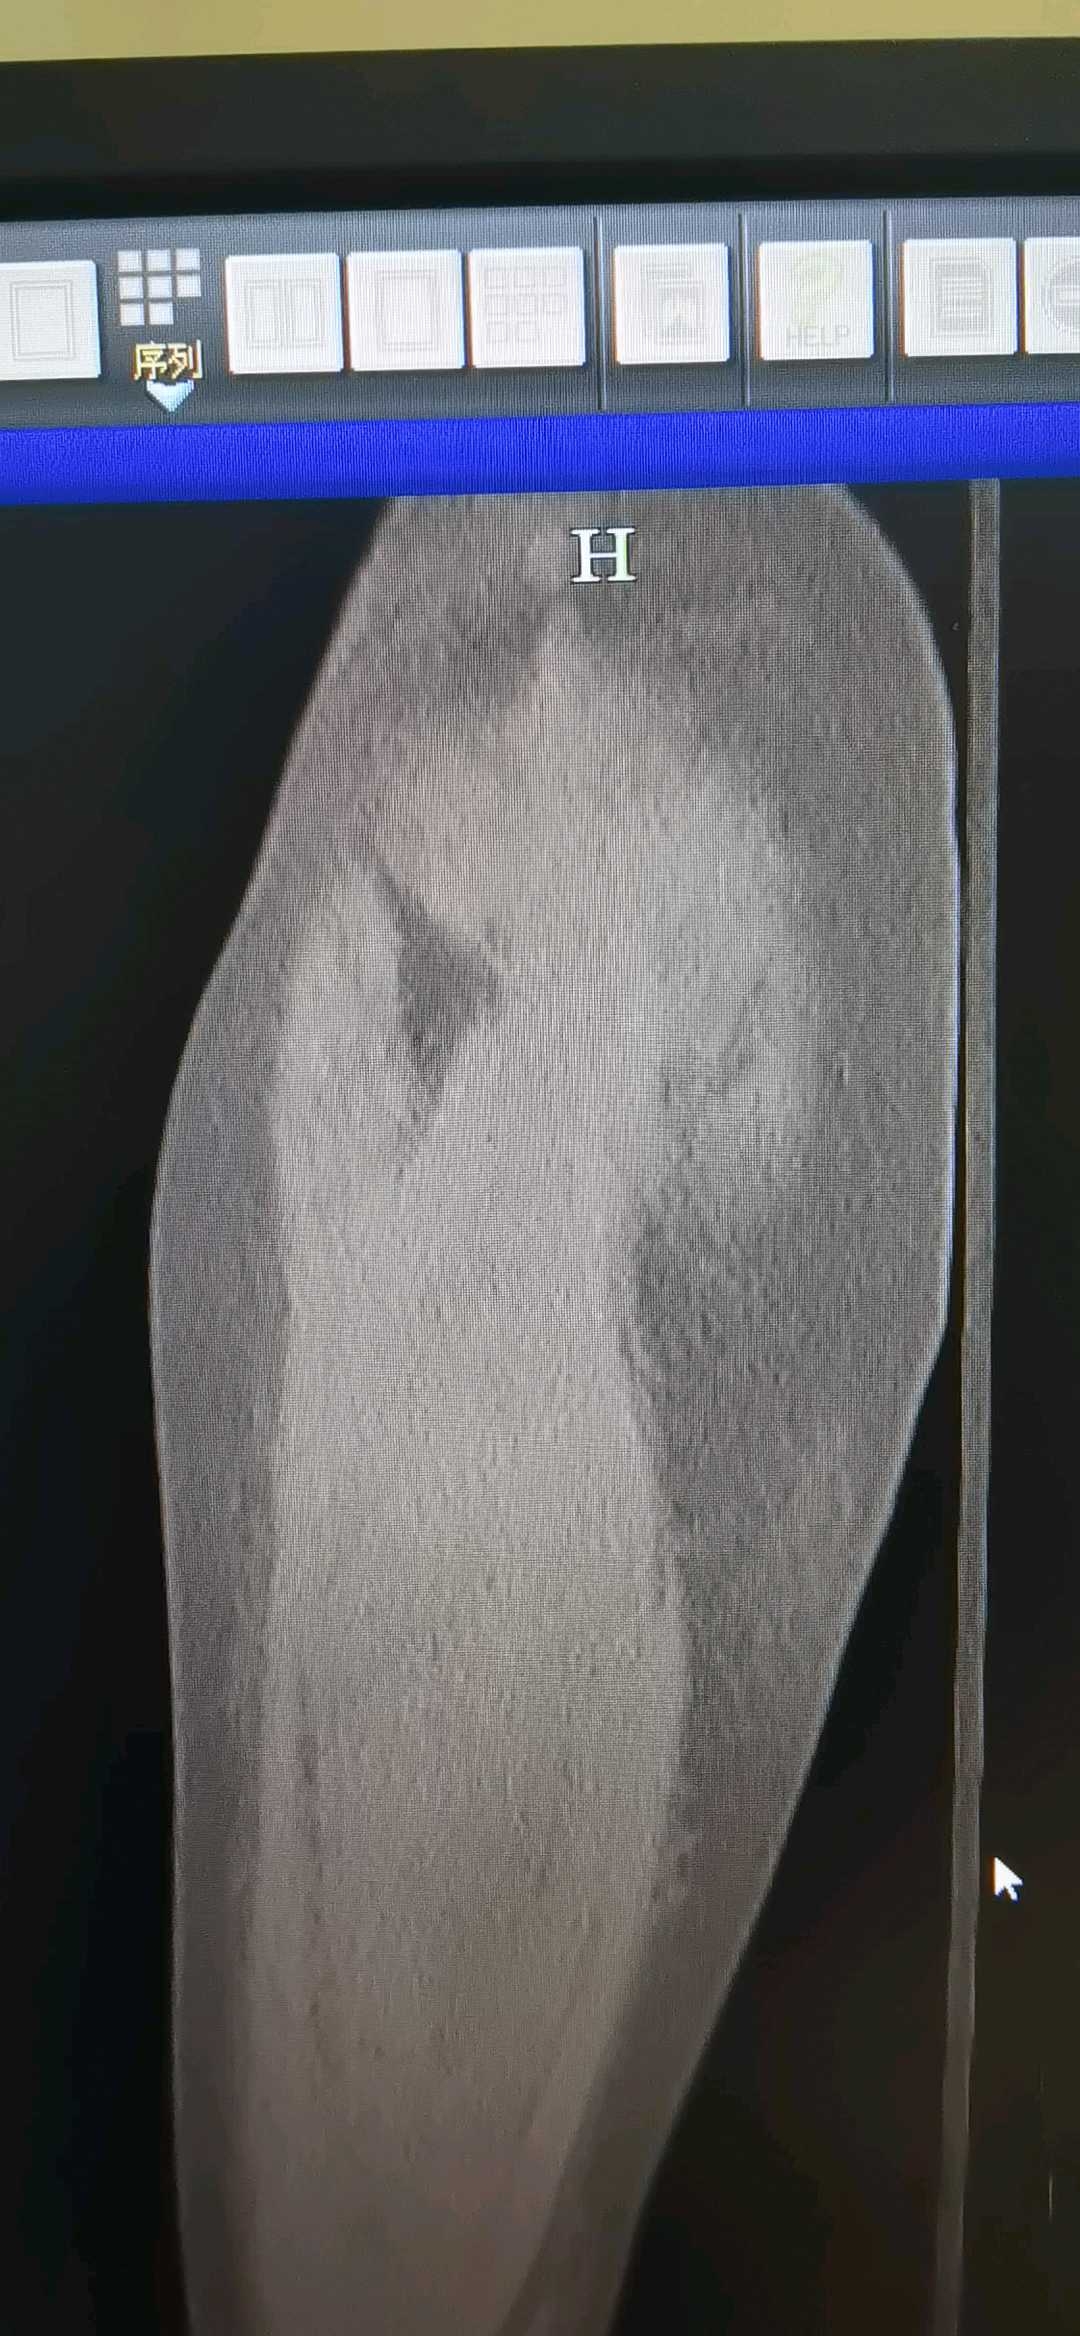

50岁单身女性,结核2年抗lao史,转子下骨折

【现病史及既往史】:2年前外院左髋关节结核手术史